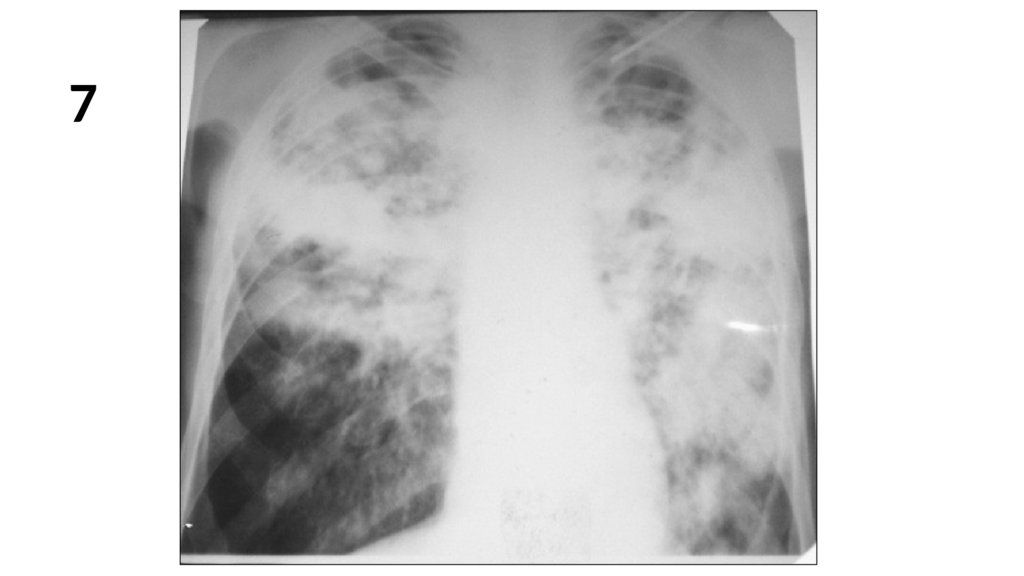

7.

7